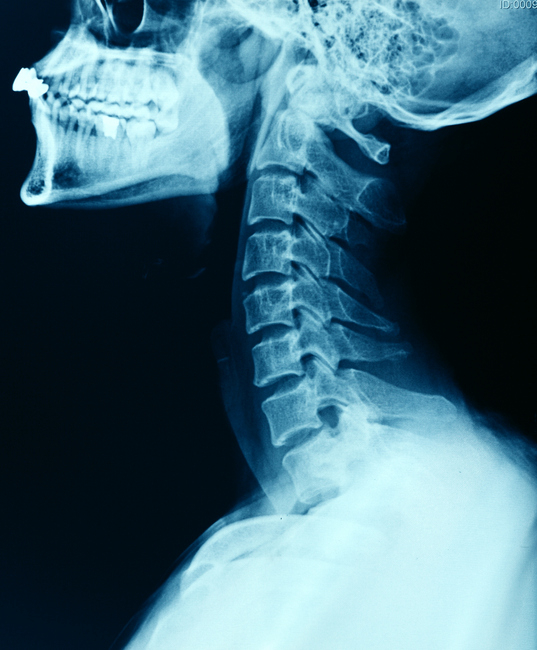

1.“Since I was a kid, I’ve heard this weird, TV static-y-sounding, rain stick-y noise coming from the back of my neck randomly. It almost feels like something is draining. I assumed that, kind of like when your stomach growls, it was just a weird body sound nobody really talked about. Well, fast-forward to this year and during a doctor’s appointment, I mentioned it offhandedly. My doctor looked absolutely horrified — she’d never heard of that in her life. I told my partner, my friends, my parents…and not a soul had any idea what the hell I was talking about.”